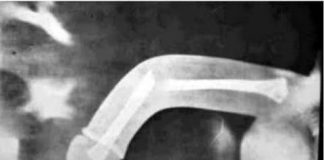

“Gãy súng” một tai nạn quý ông gặp khi làm “chuyện...

Tai nạn hy hữu này thường gặp ở những người trẻ tuổi do chưa hiểu biết về giới tính nên tự bẻ gãy khi thấy “cậu nhỏ” bất thường, hoặc gặp ở những cặp vợ chồng trẻ do quá hăng, chưa có kinh nghiệm, hay những người có ham muốn tình dục quá mức... cho dù nặng hay nhẹ thì gãy “kiếm” (dương vật) rất nguy hiểm, nếu không được chữa trị kịp thời thì sẽ để lại hậu quả nghiêm trọng, thậm chí còn bị liệt dương.